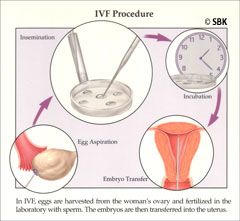

El IVF es un proceso de seis pasos. Después de la hiperestimulación ovárica controlada, se obtienen los óvulos (huevos) de los ovarios insertando una aguja de aspiración a través de la parte posterior de la vagina. Se utiliza anestesia durante este procedimiento. Los óvulos se limpian y el espermatozoide lavado del marido o del donante se anade a la gota que contiene el óvulo para la fertilización. La micromanipulación del huevo y del espermatozoide, por ejemplo si ICSI es necesario, se llevaría durante esta etapa. El huevo que ha sido fertilizado se llama cigota, y los cigotas se transforman en embriones. Los embriones se incuban en el laboratorio entre tres y cinco días. Antes de la transferencia de embriones, se lleva a cabo el procedimiento de maduración asistida para estimular la implantación.

El IVF es un proceso de seis pasos. Después de la hiperestimulación ovárica controlada, se obtienen los óvulos (huevos) de los ovarios insertando una aguja de aspiración a través de la parte posterior de la vagina. Se utiliza anestesia durante este procedimiento. Los óvulos se limpian y el espermatozoide lavado del marido o del donante se anade a la gota que contiene el óvulo para la fertilización. La micromanipulación del huevo y del espermatozoide, por ejemplo si ICSI es necesario, se llevaría durante esta etapa. El huevo que ha sido fertilizado se llama cigota, y los cigotas se transforman en embriones. Los embriones se incuban en el laboratorio entre tres y cinco días. Antes de la transferencia de embriones, se lleva a cabo el procedimiento de maduración asistida para estimular la implantación.

Paso 1: Estimulación Ovárica: se administran medicamentos hormonales inyectables, como por ejemplo, Gonal F y Follistim se dara mediante una jeringa delgada y pequeña por debajo de la piel durante varios días para estimular a los ovarios para la producción de folículos múltiples. El desarrollo de estos folículos se controla a través de ultrasonidos (o ecografías) vaginales. Cuando los folículos han madurado hasta el tamaño adecuado, se administra una inyección de otro medicamento hormonal, como por ejemplo Ovidrel, el cual funciona como la hormona luteinizante (LH) para liberar al huevo. Generalmente se lo dara el día después de la última dosis de Gonal F o Follistim, a una hora específica según las instrucciones de la doctora. Es extremadamente importante cumplir con el horario que la doctora determina. El tiempo dispuesto de fertilización in vitro depende de la dosificación adecuada de Ovidrel.

Paso 1: Estimulación Ovárica: se administran medicamentos hormonales inyectables, como por ejemplo, Gonal F y Follistim se dara mediante una jeringa delgada y pequeña por debajo de la piel durante varios días para estimular a los ovarios para la producción de folículos múltiples. El desarrollo de estos folículos se controla a través de ultrasonidos (o ecografías) vaginales. Cuando los folículos han madurado hasta el tamaño adecuado, se administra una inyección de otro medicamento hormonal, como por ejemplo Ovidrel, el cual funciona como la hormona luteinizante (LH) para liberar al huevo. Generalmente se lo dara el día después de la última dosis de Gonal F o Follistim, a una hora específica según las instrucciones de la doctora. Es extremadamente importante cumplir con el horario que la doctora determina. El tiempo dispuesto de fertilización in vitro depende de la dosificación adecuada de Ovidrel.

Paso 2: Recolección/Procesamiento del Semen: un poco tiempo antes de la extracción del huevo, se colectara y procesará una muestra de semen para aislar a los espermatozoides más activos y resistentes. Estos espermatozoides se colocarán junto a cada huevo aspirado. Nosotros recomendamos a los pacientes considerar congelar una muestra de semen con varias semanas de anticipación de la fecha de la extracción del huevo por varias razones. La coordinación de los horarios del trabajo y de la cirugía puede resultar difícil o puede enfermarse repentinamente. Además, la noción de tener que obtener una muestra el día en el cual se realiza la extracción del huevo puede resultar estresante.

Paso 2: Recolección/Procesamiento del Semen: un poco tiempo antes de la extracción del huevo, se colectara y procesará una muestra de semen para aislar a los espermatozoides más activos y resistentes. Estos espermatozoides se colocarán junto a cada huevo aspirado. Nosotros recomendamos a los pacientes considerar congelar una muestra de semen con varias semanas de anticipación de la fecha de la extracción del huevo por varias razones. La coordinación de los horarios del trabajo y de la cirugía puede resultar difícil o puede enfermarse repentinamente. Además, la noción de tener que obtener una muestra el día en el cual se realiza la extracción del huevo puede resultar estresante.

Paso 3: Extracción del Huevo: El doctor aspira cada folículo maduro con una aguja guiada por ultrasonido. El procedimiento se lleva con sedación administrada por un anestesiólogo matriculado y en una sala especial de extracción de huevos con filtración de aire. Esto generalmente se realiza a través de la parte posterior de la pared vaginal pero en ocasiones raras, puede llevarse a cabo por el abdomen. Los huevos aspirados luego se transfieren al embriólogo para que realice la identificación y fertilización.

Paso 3: Extracción del Huevo: El doctor aspira cada folículo maduro con una aguja guiada por ultrasonido. El procedimiento se lleva con sedación administrada por un anestesiólogo matriculado y en una sala especial de extracción de huevos con filtración de aire. Esto generalmente se realiza a través de la parte posterior de la pared vaginal pero en ocasiones raras, puede llevarse a cabo por el abdomen. Los huevos aspirados luego se transfieren al embriólogo para que realice la identificación y fertilización.

Paso 4: Evaluación de la Fertilización: 14 a 18 horas después de que el espermatozoide y el huevo se colocan juntos, son evaluados por el embriólogo para que confirme la fertilización. Si ocurre la fertilización, los cigotos (o huevos fertilizados) se cultivan para prepararlos para la transferencia (o implantación) del embrión. Durante los próximos días el embriólogo observara continuadamente y determinará la calidad del embrión. La calidad del embrión determinará cuándo se llevará a cabo la transferencia de embriones y la cantidad de embriones que se transferirán. Dependiendo del número de huevos fertilizados, algunos pueden congelarse para su utilización en un proximo ciclo.

Paso 4: Evaluación de la Fertilización: 14 a 18 horas después de que el espermatozoide y el huevo se colocan juntos, son evaluados por el embriólogo para que confirme la fertilización. Si ocurre la fertilización, los cigotos (o huevos fertilizados) se cultivan para prepararlos para la transferencia (o implantación) del embrión. Durante los próximos días el embriólogo observara continuadamente y determinará la calidad del embrión. La calidad del embrión determinará cuándo se llevará a cabo la transferencia de embriones y la cantidad de embriones que se transferirán. Dependiendo del número de huevos fertilizados, algunos pueden congelarse para su utilización en un proximo ciclo.

Paso 6: Transferencia (o Implantación) del Embrión: este procedimiento fragil e minimo, es realizado por un doctor que coloca un catéter que fue cargado con una cantidad seleccionada de embriones por el embriólogo, a través del cérvix y dentro del útero para depositar los embriones allí. Cuando es posible, se realizan transferencias de blastocistos, lo cual ocurre alrededor del día cinco del crecimiento embrionario. Las transferencias de blastocistos permiten la implantación de un embrión más maduro, y de esa manera, el embriólogo puede seleccionar menos embriones para transferir, logrando una alta tasa de embarazos con un menor riesgo de gestaciones múltiples superiores a los gemelos. Ocasionalmente, en la etapa de división, el embriólogo recomienda la transferencia en el día tres del crecimiento embrionario basándose en la calidad del embrión.

Paso 6: Transferencia (o Implantación) del Embrión: este procedimiento fragil e minimo, es realizado por un doctor que coloca un catéter que fue cargado con una cantidad seleccionada de embriones por el embriólogo, a través del cérvix y dentro del útero para depositar los embriones allí. Cuando es posible, se realizan transferencias de blastocistos, lo cual ocurre alrededor del día cinco del crecimiento embrionario. Las transferencias de blastocistos permiten la implantación de un embrión más maduro, y de esa manera, el embriólogo puede seleccionar menos embriones para transferir, logrando una alta tasa de embarazos con un menor riesgo de gestaciones múltiples superiores a los gemelos. Ocasionalmente, en la etapa de división, el embriólogo recomienda la transferencia en el día tres del crecimiento embrionario basándose en la calidad del embrión.